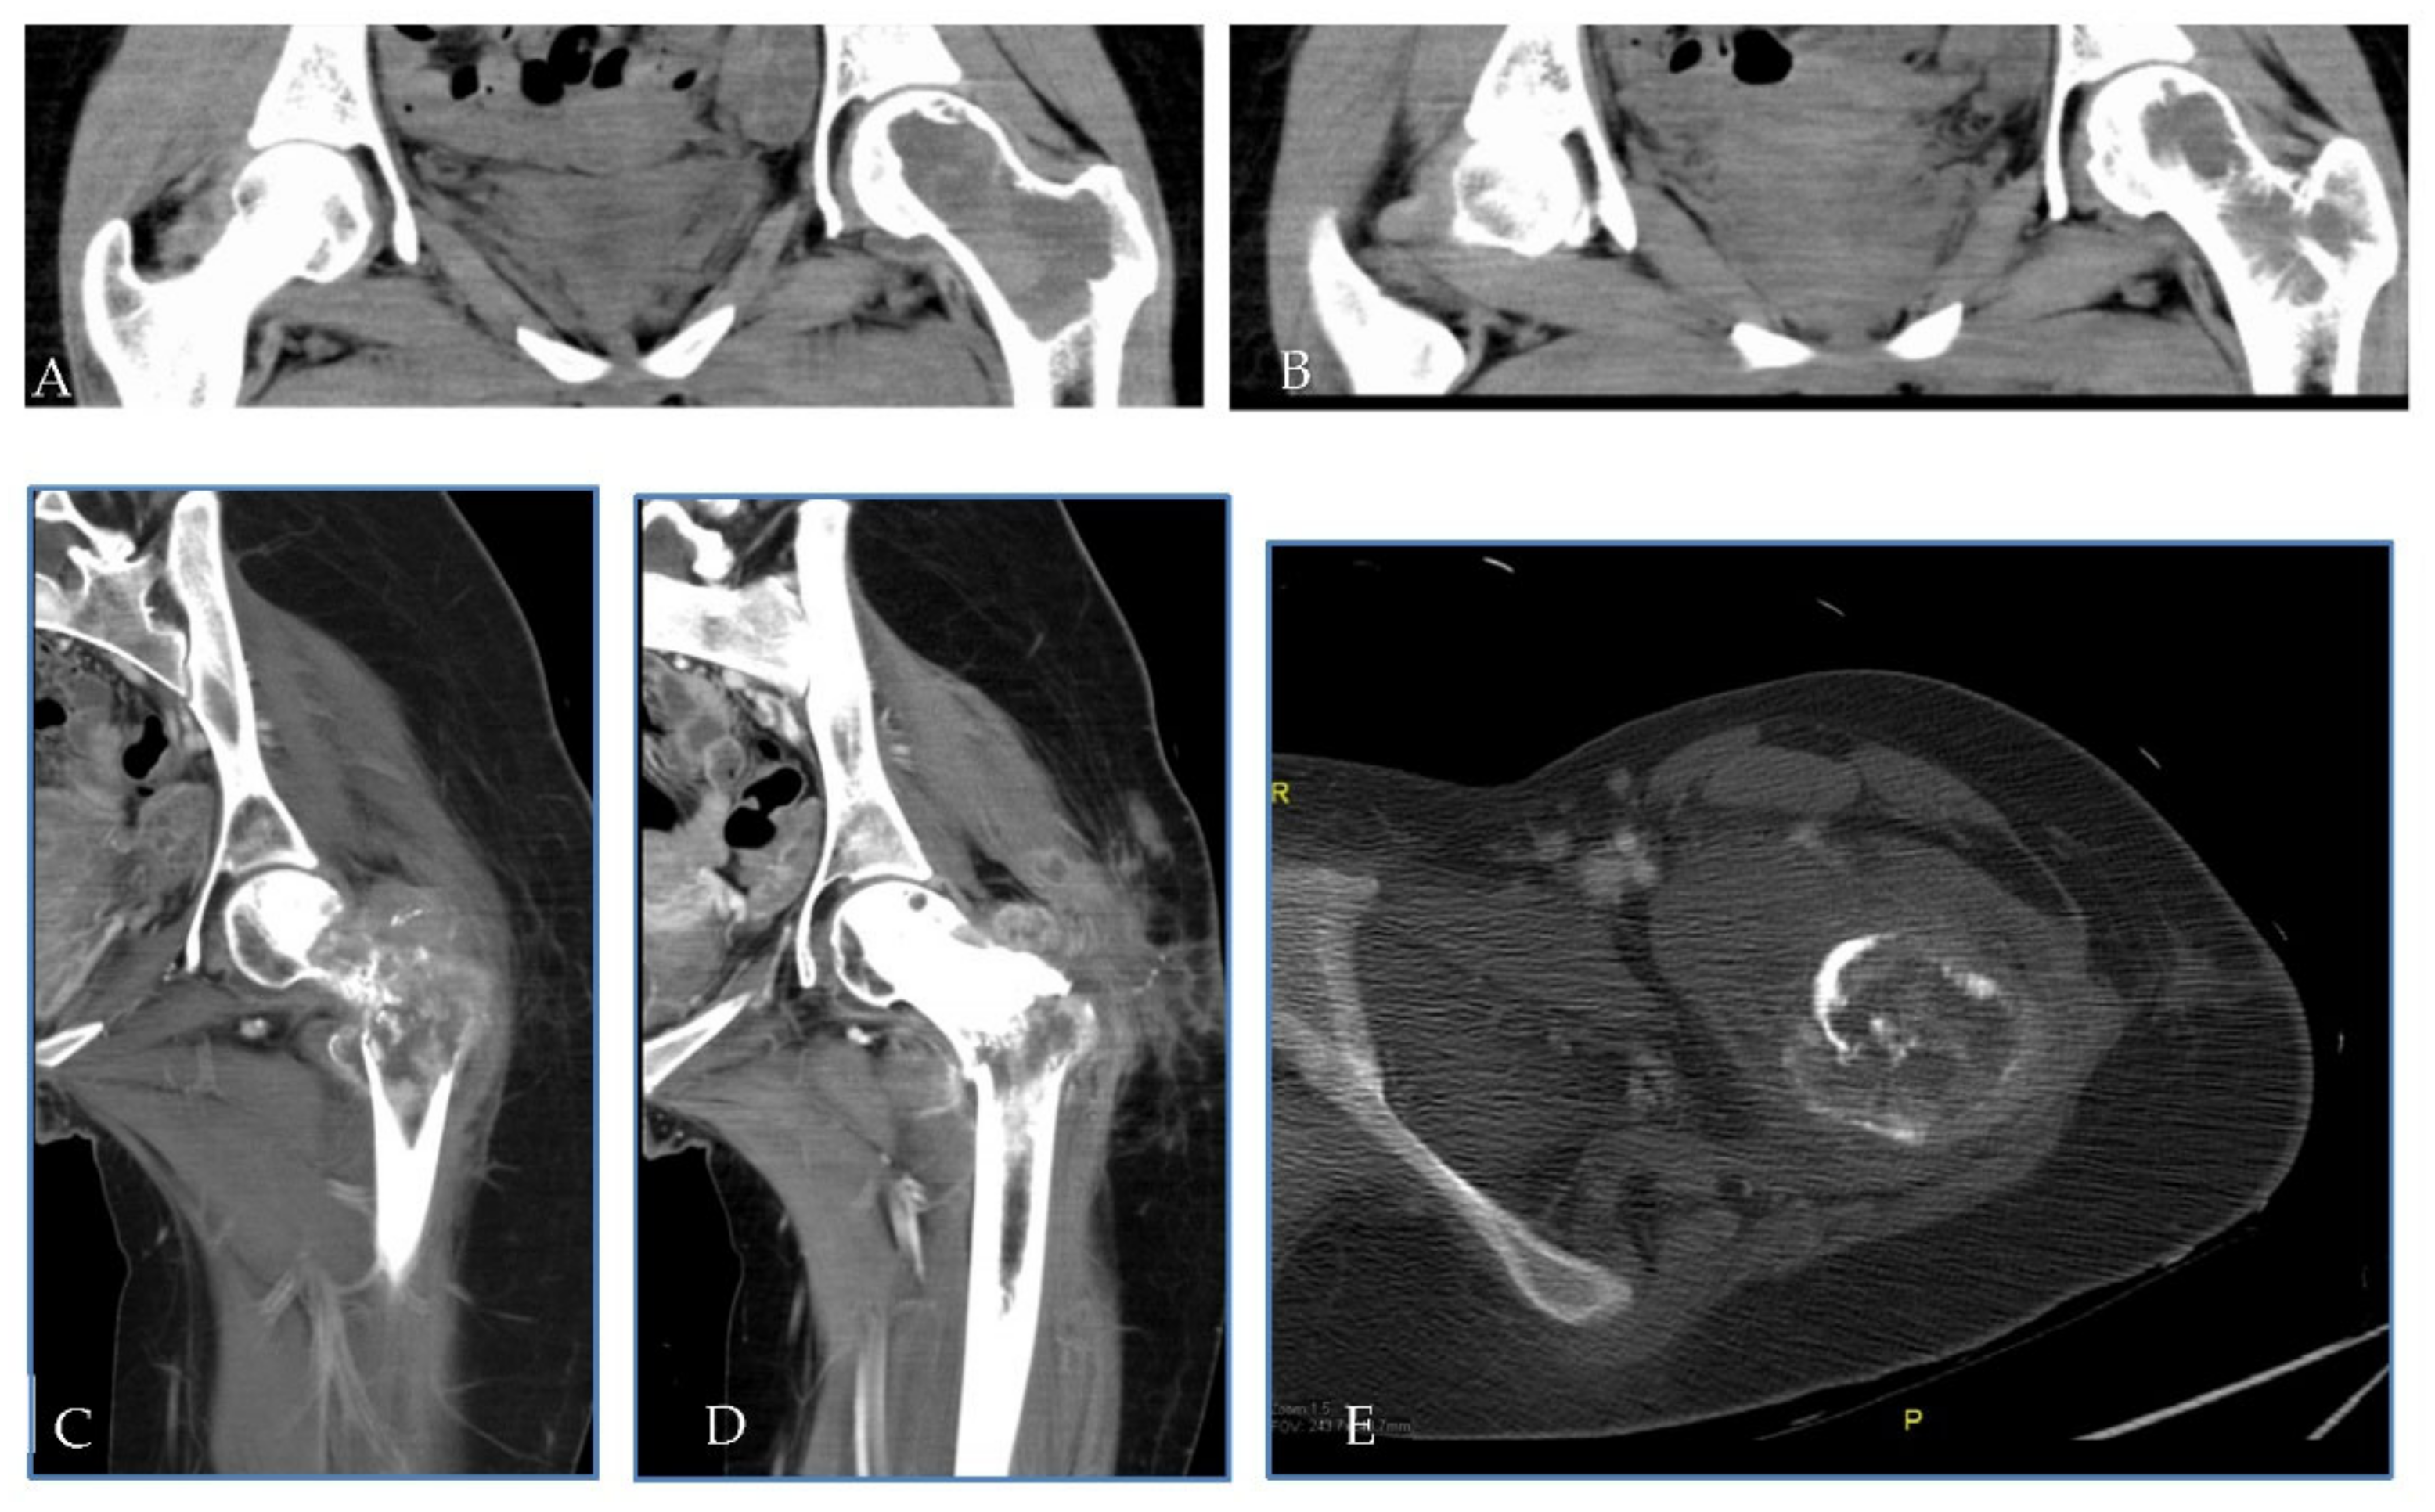

2.1. Patient 1

| Pt 1 | 29 | F | 0 | 17 July | Right femur | Curettage and bone grafts | 18 February | Neoadj denosumab (7 cycles) | 18 July Extraarticular resection: high-grade fibroblastic osteosarcoma | ISG/OS-2 | PD | I: IFO II: GEM.TXT III: PAZO | D 22 January | 9 | 53 | 43 |